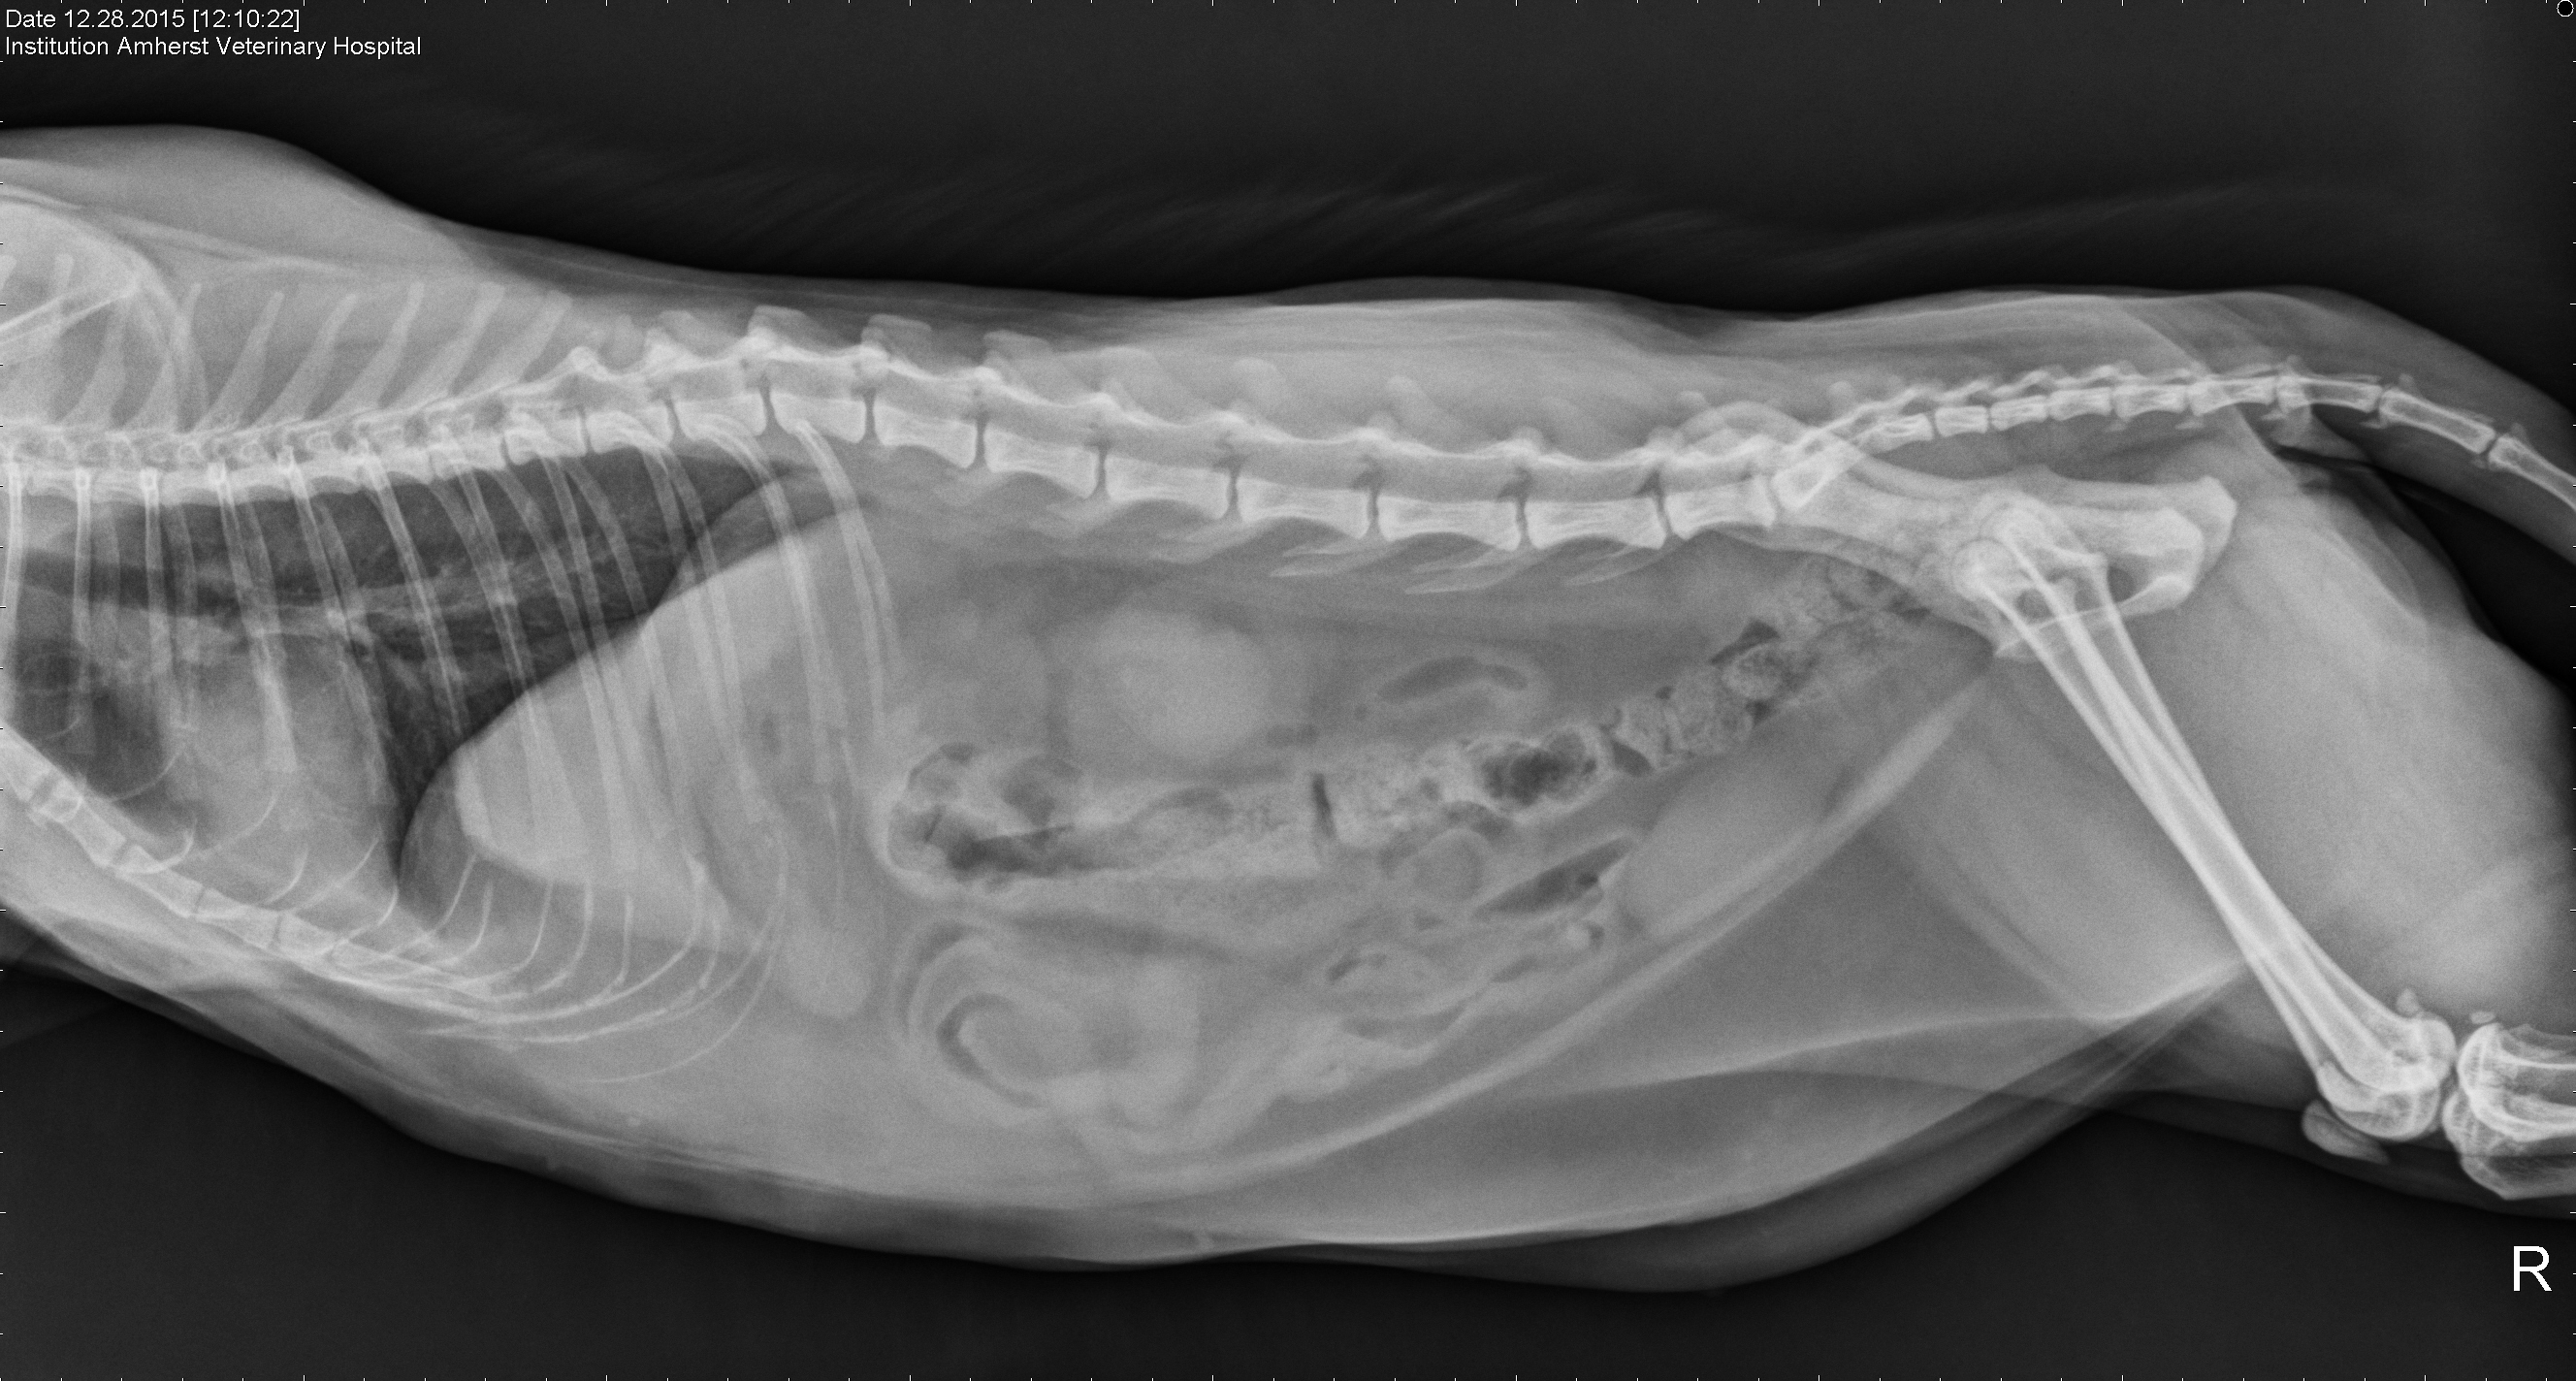

Here she comes again.  There was a problem.  These are the details.

R Lat Abdomen

Your animal on speed.  This is what it looks like.  Bounding over the main.  Running and disporting and displaying.  Amphetamine isn’t what it used to be.  What I think he meant is rarely is it used now to treat blockages in your head.  Heart.  Lungs.  Digestive tract.

We’re puzzled.  It’s too much information but when your animal goes down you act.  It’s your fur, your animal, your time.  Time to get to the vet.

Everything’s okay.  Eating again.  Good bowels.  Great images.  Dear Fuie back on form.